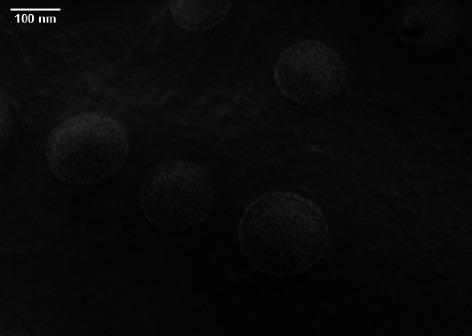

在全球范围内,葡萄球菌治疗的临床挑战正在增加,因此找到有效的策略来阻止耐药分离株,特别是耐甲氧西林金黄色葡萄球菌(MRSA)的传播至关重要。Niosomal给药系统以其控释特性和其他优势而闻名,可以提高负载药物的抗菌能力。本研究旨在通过检测桃金娘烯醇负载的niosomal system对MRSA分离株的抗菌和抗生物膜特性,提出一种对抗葡萄球菌耐药挑战的新型药物传递系统。采用薄膜水化法制备niosomal制剂,并通过包封效率(EE %)、体外释放谱、场发射扫描电镜(FE-SEM)和动态光散射(DLS)对其理化特性进行评价。此外,测定了最低抑菌浓度(mic)和最低杀菌浓度(MBCs),并与游离桃金娘烯醇进行了比较,以评估配制的niosomal myrtenol抗mrsa的活性。此外,通过检测生物膜最低抑制和根除浓度(BMIC/BMEC),研究了含有桃金娘烯醇的niosome对MRSA生物膜的有效性。此外,还对合成的乳质体对人包皮成纤维细胞系(HFF)的细胞毒性进行了评价。FE-SEM结果表明,负载桃金娘烯醇的乳质体为球形,直径为122.1 nm,而DLS报道的水动力尺寸为130.8 nm。制备的乳质体制剂的表面电荷和EE%分别为-53.6 mV和62.90%。与游离桃金娘烯醇制剂相比,niosomal myrtenol制剂显示出更高的抗菌活性。此外,负载桃金娘烯醇的乳质体降低了所有MRSA分离株的生物膜形成潜力,并在同等浓度的非乳质体制剂下有效地根除了细菌生物膜。根据这项研究,乳小体由于几个有利的特性,包括缓释、无毒、小尺寸和高EE%,表现出很高的药物递送潜力。Niosomal递送系统通过增强游离桃金娘烯醇的抗菌和抗生物膜活性,提出了一种对抗细菌感染的新方法,特别是由MRSA分离物引起的细菌感染。

The clinical challenge of staphylococcal treatment is increasing globally, making it critical to find effective strategies to hinder the spread of resistant isolates, particularly methicillin-resistant Staphylococcus aureus (MRSA). Niosomal drug delivery systems, known for their controlled release profiles and other advantageous features, can enhance the efficacy of antimicrobial ability of loaded agents. This study aims to propose a novel drug delivery system for combating staphylococcal resistance challenge through examining the antibacterial and antibiofilm properties of myrtenol-loaded niosomal system against MRSA isolates. The niosomal formulation was prepared using the thin-film hydration process, and its physicochemical characteristics were assessed through entrapment efficiency (EE %), in vitro release profile, field-emission scanning electron microscopy (FE-SEM), and dynamic light scattering (DLS). In addition, minimum inhibitory concentrations (MICs) and minimum bactericidal concentrations (MBCs) were measured and compared with free myrtenol to evaluate the anti-MRSA activity of the formulated niosomal myrtenol. Furthermore, the effectiveness of niosome containing myrtenol against MRSA biofilms was investigated by examining biofilm minimum inhibitory and eradication concentrations (BMIC/BMEC). Additionally, the cytotoxicity of synthesized niosomes was assessed on the human foreskin fibroblast cell line (HFF). Results from FE-SEM showed that myrtenol-loaded niosomes were spherical with a diameter of 122.1 nm, while the hydrodynamic size reported from DLS was 130.8 nm. The surface charge and EE% of the prepared niosomal formulation were -53.6 mV and 62.90%, respectively. The niosomal myrtenol formulation demonstrated the increased antibacterial activity in comparison with free myrtenol formulation. Furthermore, myrtenol-loaded niosomes reduced the biofilm formation potential in all MRSA isolates and effectively eradicated bacterial biofilms at equivalent concentrations of the non-niosomal formulation. According to this study, niosomes exhibit high potential for drug delivery due to several favorable characteristics, including a sustained-release profile, nontoxicity, small size, and high EE%. Niosomal delivery system presents a novel approach to combat bacterial infections, particularly those caused by MRSA isolates by enhancing antibacterial and antibiofilm activities of free myrtenol.